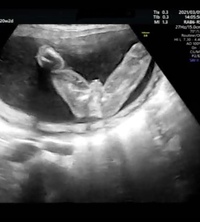

赤ちゃんの性別判定が男の子から女の子に変わることってあるの?そんな疑問に答えます。 18週のスクリーニング検査で女の子かな?22週の健診の時に男の子かな?と言われ、26週で女の子確定でした。途中、どっちやねーん! エコー検査で何度か先生妊娠週 18w0d BPD (頭の幅) 453ミリ AC (腹部周囲長) 1292ミリ FL (大腿骨長) 251ミリ 体重は225グラム、頭からお尻まで13センチで足を伸ばせばセンチ弱とのこと。 順調だそうです♪ 『ぜひとも性別をお願いします! 』で、エコー開始数秒で写真の通り男の子と

妊娠18週3日~とうとう性別判明! 股おっぴろげ写真公開! (注:長文) ☆ HAPPY LIFE ☆ 妊娠18週3日~とうとう性別判明! 股おっぴろげ写真公開! (注:長文) 7月27日(月) <妊娠18週3日> 良好。 でもお腹が張って酷い。妊娠16週に女の子だとわかり、嬉しさとほっとした気持ちでした。 早い時期ですと、妊娠16週ごろに性別が判明したケースが多いようです。ちょうど安定期に入る時期で、ママに心の余裕が出るころでもありますね。 妊娠18週 シンボルが見えた17週のエコー検査で、性別が分かるのはまだ先だろうなと思っていると、先生からもう分かるよ~と言われ見せてもらうことに。 先生から性別が女の子と聞いた時、びっくりしました。 18週の健診の時に、エコーでそれらしきものが見えたのですが

妊娠30週目の女の子のエコー写真 女の子を見分けるのは足の間の突起物が無いかコーヒー豆が見えるか! 女の子の性別判定はいつから可能? 女の子の性別判定はいつから可能なのでしょうか? 男の子も女の子も外性器がしっかりと形成され、 性別判定6分 助産師 妊娠18週は胎動を初めて感じたり、赤ちゃんの性別が判明するなど楽しみがたくさん。 妊娠5か月目にはいり、つわりや妊娠初期症状が落ち着いて